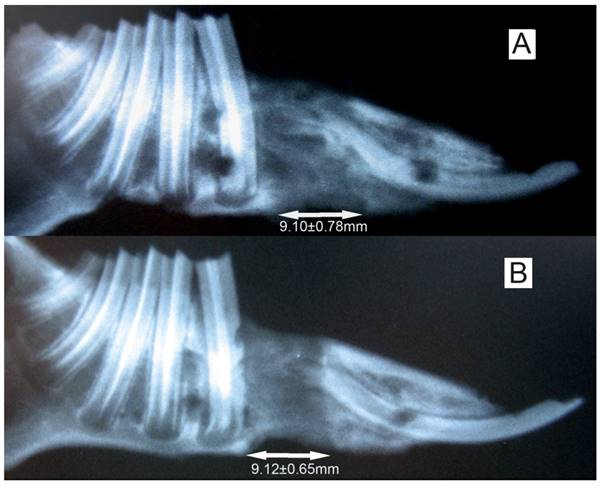

Radiographs showed that the distraction gap was filled with new bone in all of the animals. There was a lower density of the new bone on the experimental side than on the control side (Fig. 3). BMD of the new bone in the distraction gap on the experimental side was 0.46±0.07g/cm2, which is significantly lower (P<0.05) than on the control side (0.61±0.09 g/cm2) (Fig. 4).

Fig 3

The X-ray of the elongated mandibular on the consolidation time of 28 days. (A) the denervation side; (B) the control side. The arrows denote the elongated bone tissue. Lengthening of 9.11±0.69 mm was successfully achieved, and no difference (P>0.05) in regenerated bone dimensions was observed between the both sides of mandibles.